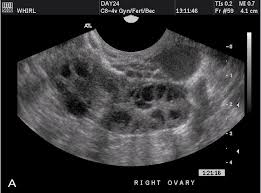

Stay informed, educate patients, be alert for risk factors, encourage screening, and treat them with compassionate care. The reason for this is that the cysts in pcos are a cluster of simple cysts that can give the appearance on imaging as one (larger) cyst with septations. Only 22% for other women. Women with pcos have a hormonal imbalance and metabolism problems that may affect their health. The condition is common among women of reproductive age and can include symptoms such as an irregular menstrual cycle, acne, thinning hair and weight gain. Why women with this disease may have a higher exposure or higher infection rate is not known. Ovarian cysts and pcos are related conditions with many of the same symptoms, meaning that women often confuse the two, or wrongly believe that they have pcos when they do not. In fact, half of women with pcos get pregnant without any medical intervention. Many symptoms of ovarian cancer are hard to recognise as they are similar to conditions such as irritable bowel syndrome (ibs). The danish cohort study found a link between pcos and endometrial cancer; Pylori in women with polycystic ovarian syndrome was nearly double the rate for other women. Here we will dispel five myths about pcos. Polycystic ovaries can be misinterpreted as complex cysts.

Polycystic Ovary Syndrome Office On Women S Health from owh-wh-d9-dev.s3.amazonaws.com In fact, half of women with pcos get pregnant without any medical intervention. Multiple cysts in the ovaries. If there is a follicle greater than 10 mm in diameter, the scan. Alan copperman, medical director at progyny , tells bustle. Stay informed, educate patients, be alert for risk factors, encourage screening, and treat them with compassionate care. Pcos can be difficult to diagnose because some of its symptoms have a variety of potential causes. Ovarian cysts are common among women of all ages. By understanding a patient's family history and lifestyle, the nurse can encourage patients to take action that supports their health and.